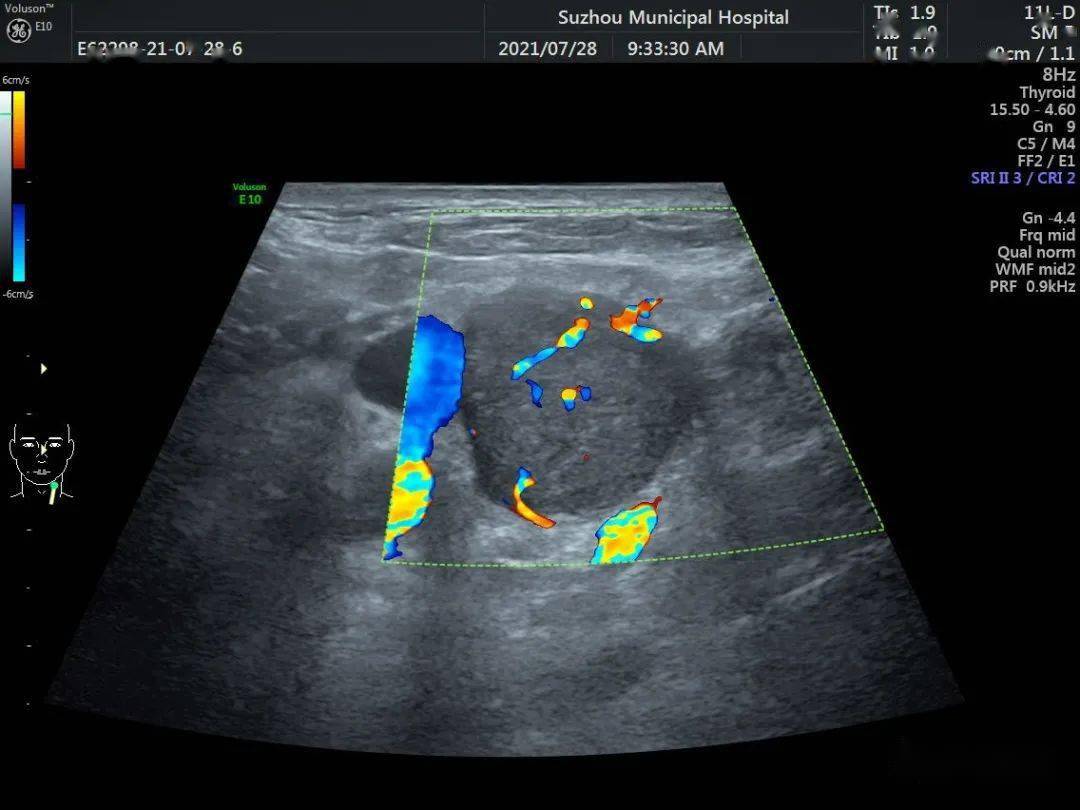

图1 甲状腺胶质囊肿内部胶态晶体后方的"彗星尾征".

甲状腺结节横轴声像图,其内见数个点状强回声灶,至少 个见彗星尾征

颈部淋巴结转移沙粒状钙化彗星尾征77甲状腺内大部分为良性病变,有

内部回声均匀(如图1),网状或蜂窝状,彗星尾征等,而恶性甲状腺结

77甲状腺内大部分为良性病变,有点状强回声伴彗星尾征,但是也有少数